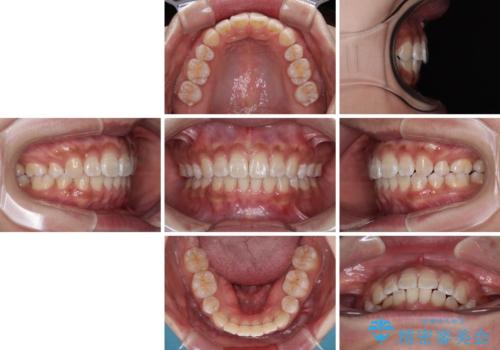

くちばしのような前歯 抜歯矯正で口を閉じやすく

強い咬合力により前歯の隙間がなかなか閉じられず、治療期間は長いものとなりましたが、横顔の印象が大きく変わるほど口元の印象を改善することができました。